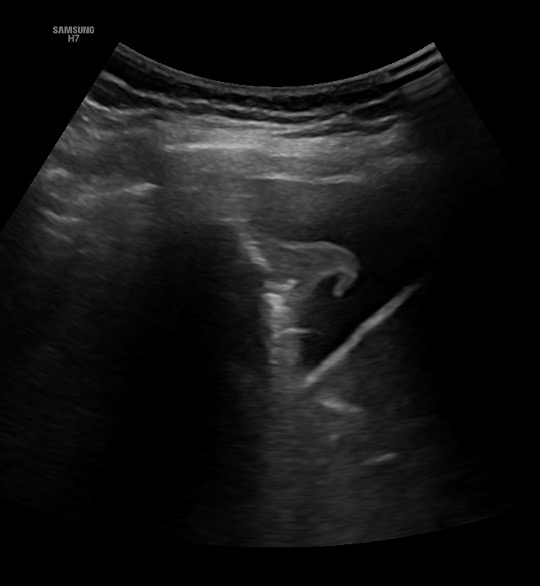

Ecografía clínica pulmonar: infiltrado en base izquierda con mínimo derrame y características de broncograma dinámico. Derrame pleural derecho de escasa cuantía con signo de la medusa.

La paciente ingresa en planta por insuficiencia respiratoria. Gracias a la ecografía clínica se objetivó en base izquierda una imagen compatible con neumonía basal izquierda. Al alta la paciente presenta mejoría clínica, ventilatoria, oximétrica y analítica con buen estado general. Eupneica en reposo y afebril.